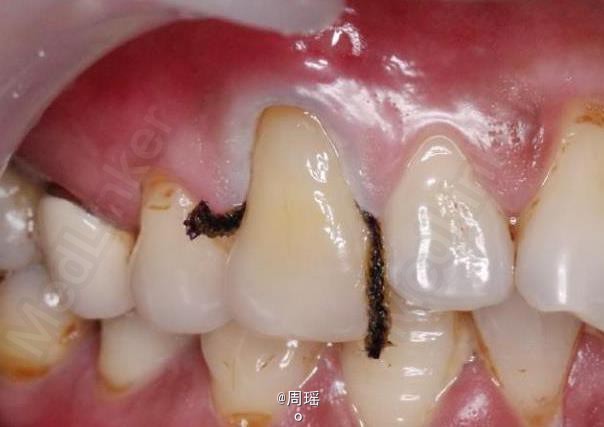

楔状缺损的充填

楔状缺损

患者,男,40岁,左上第一前磨牙楔状缺损来诊。平素体质一般,无系统性疾病和高血压、心脏病等病史,无药物、食物过敏史。